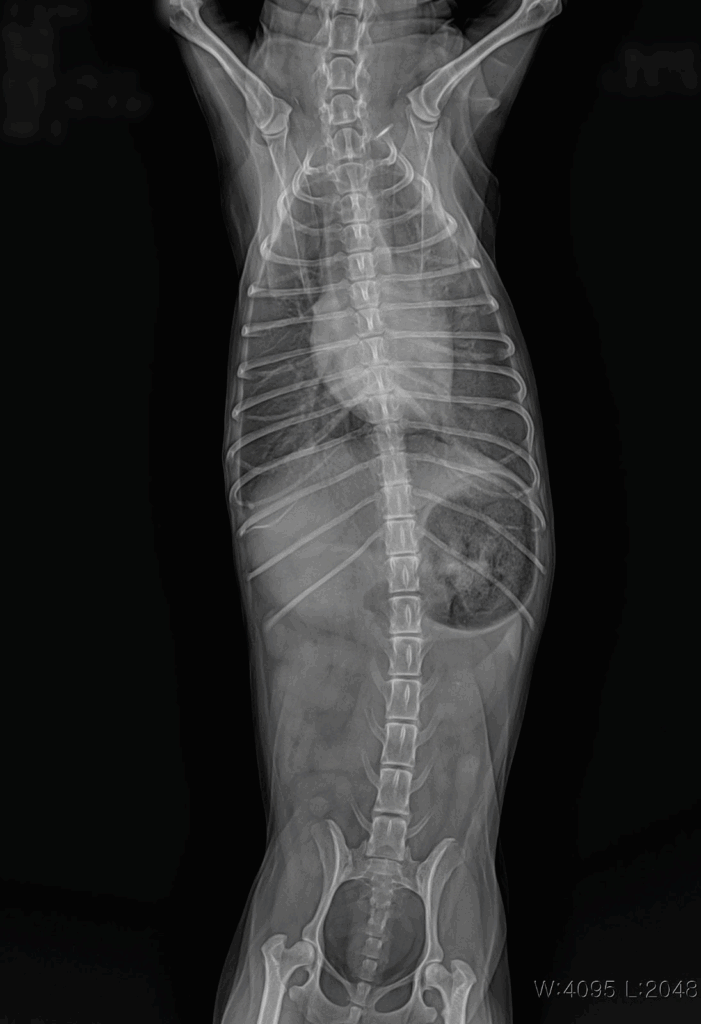

📌 흉부 X-ray

X-ray 촬영은 심장의 크기와 모양, 그리고 폐에 물이 차 있는지 여부를 확인하는 데 사용됩니다. 이를 통해 심장비대나 폐수종 같은 합병증 여부를 빠르게 파악할 수 있습니다.

내원 당시 흉부 방사선 사진: 심장 비대 및 폐수종 확인

검사 결과 심부전 소견이 확인되었고, 이에 따라 약물 관리를 통한 환축 안정화를 목표로 치료를 시작했습니다.

흉부 방사선 촬영에서도 폐수종 소견이 호전되어, 환축이 안정된 상태로 생활할 수 있게 되었습니다.